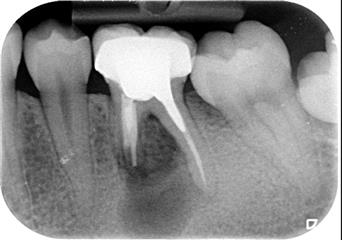

Incision d'un abcès dentaire